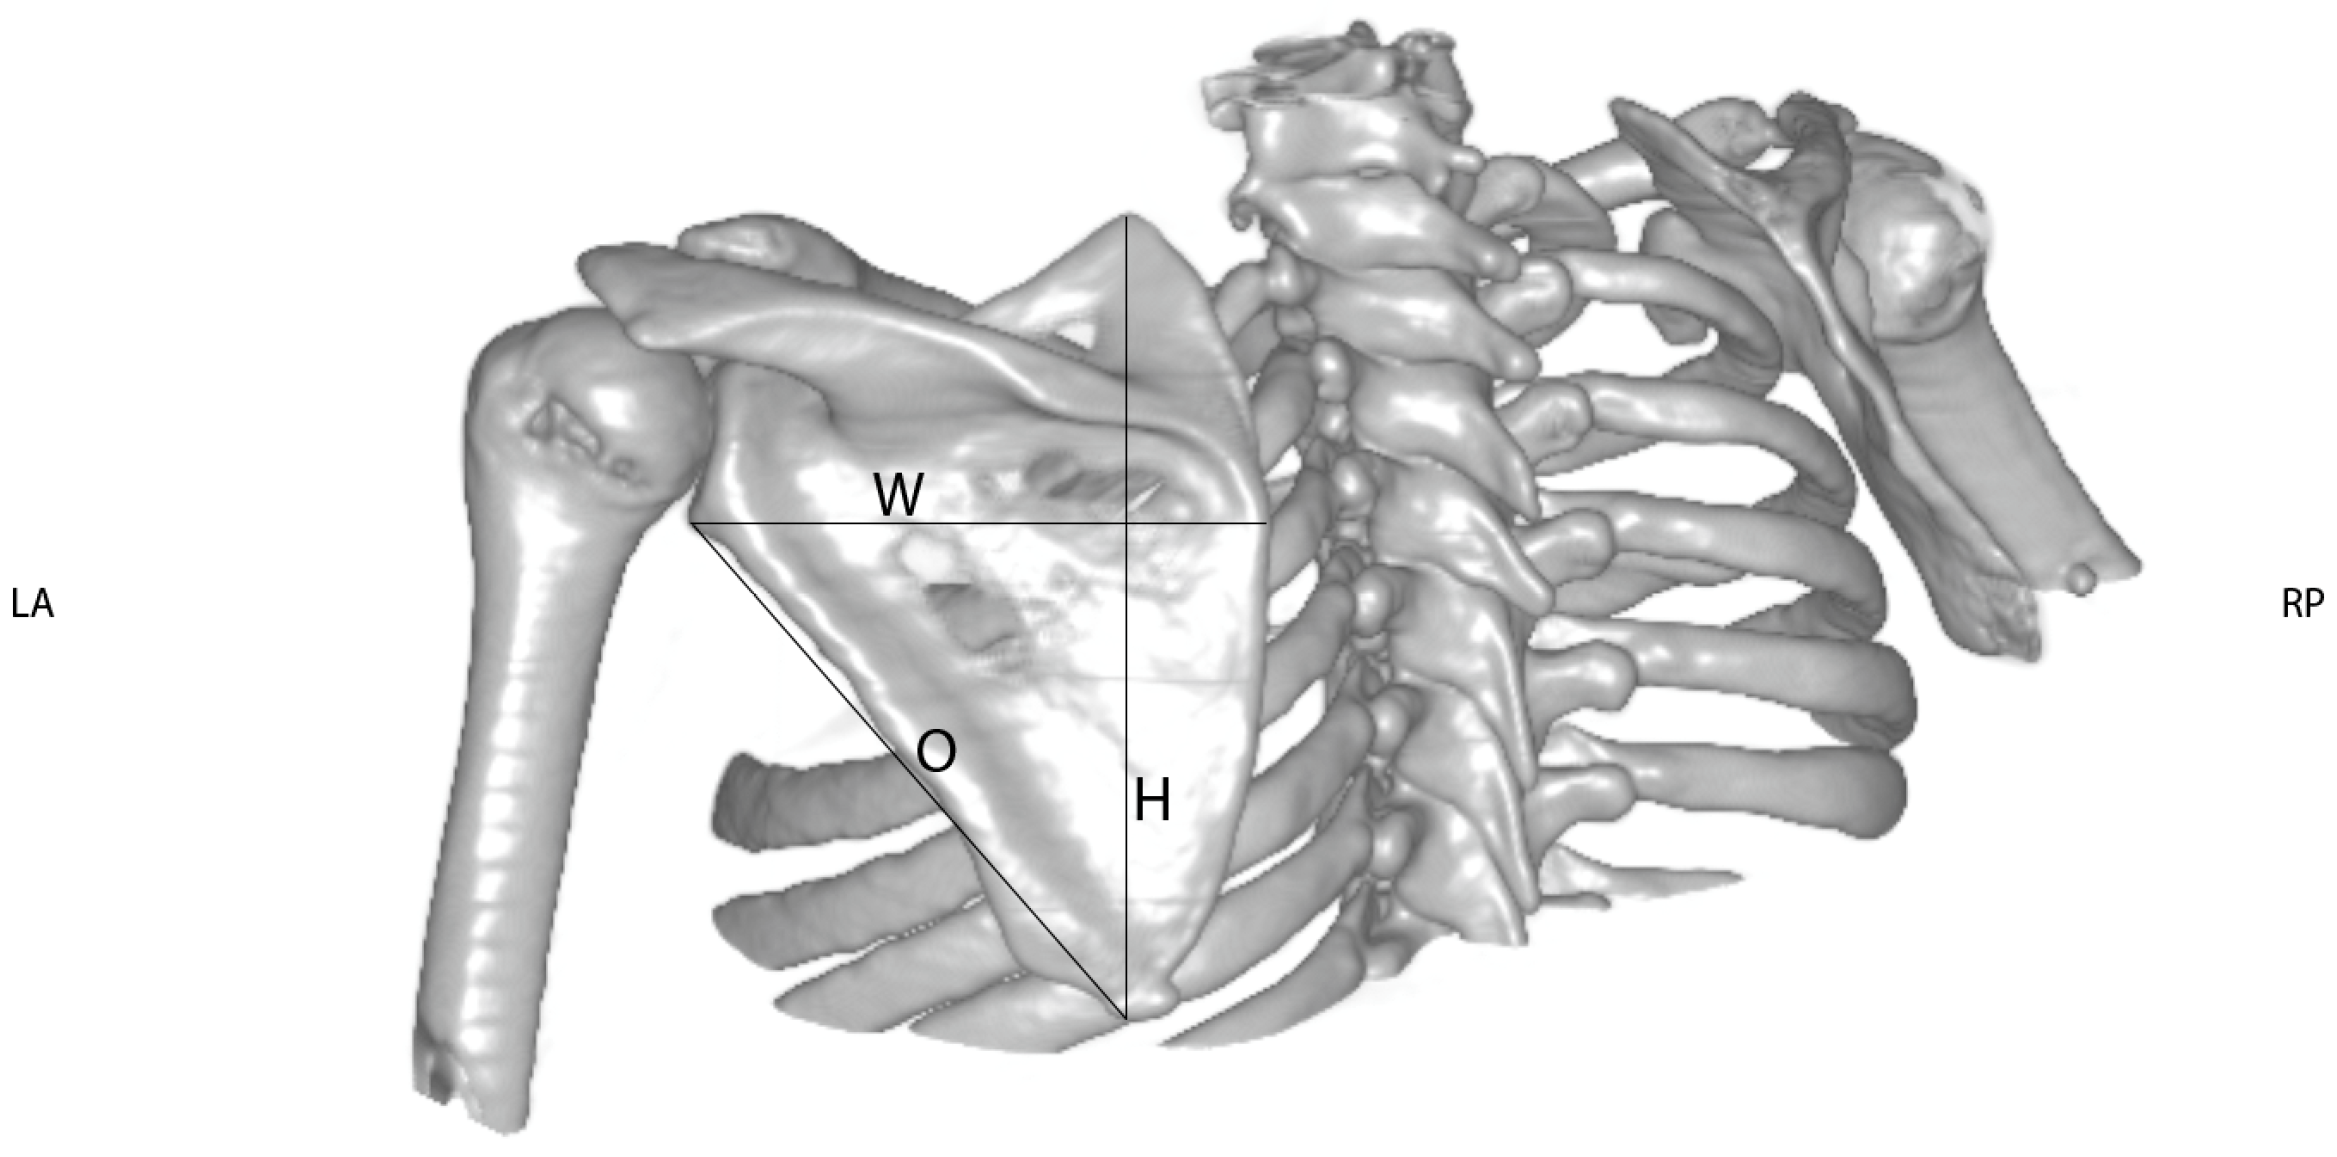

2. Materials and Methods